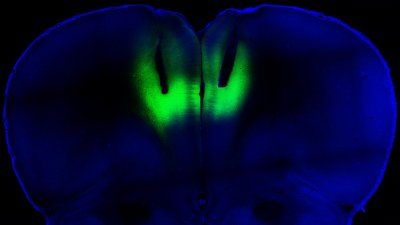

Archive: Brain Mapping Reveals Neurological Basis of Decision-Making in Rats